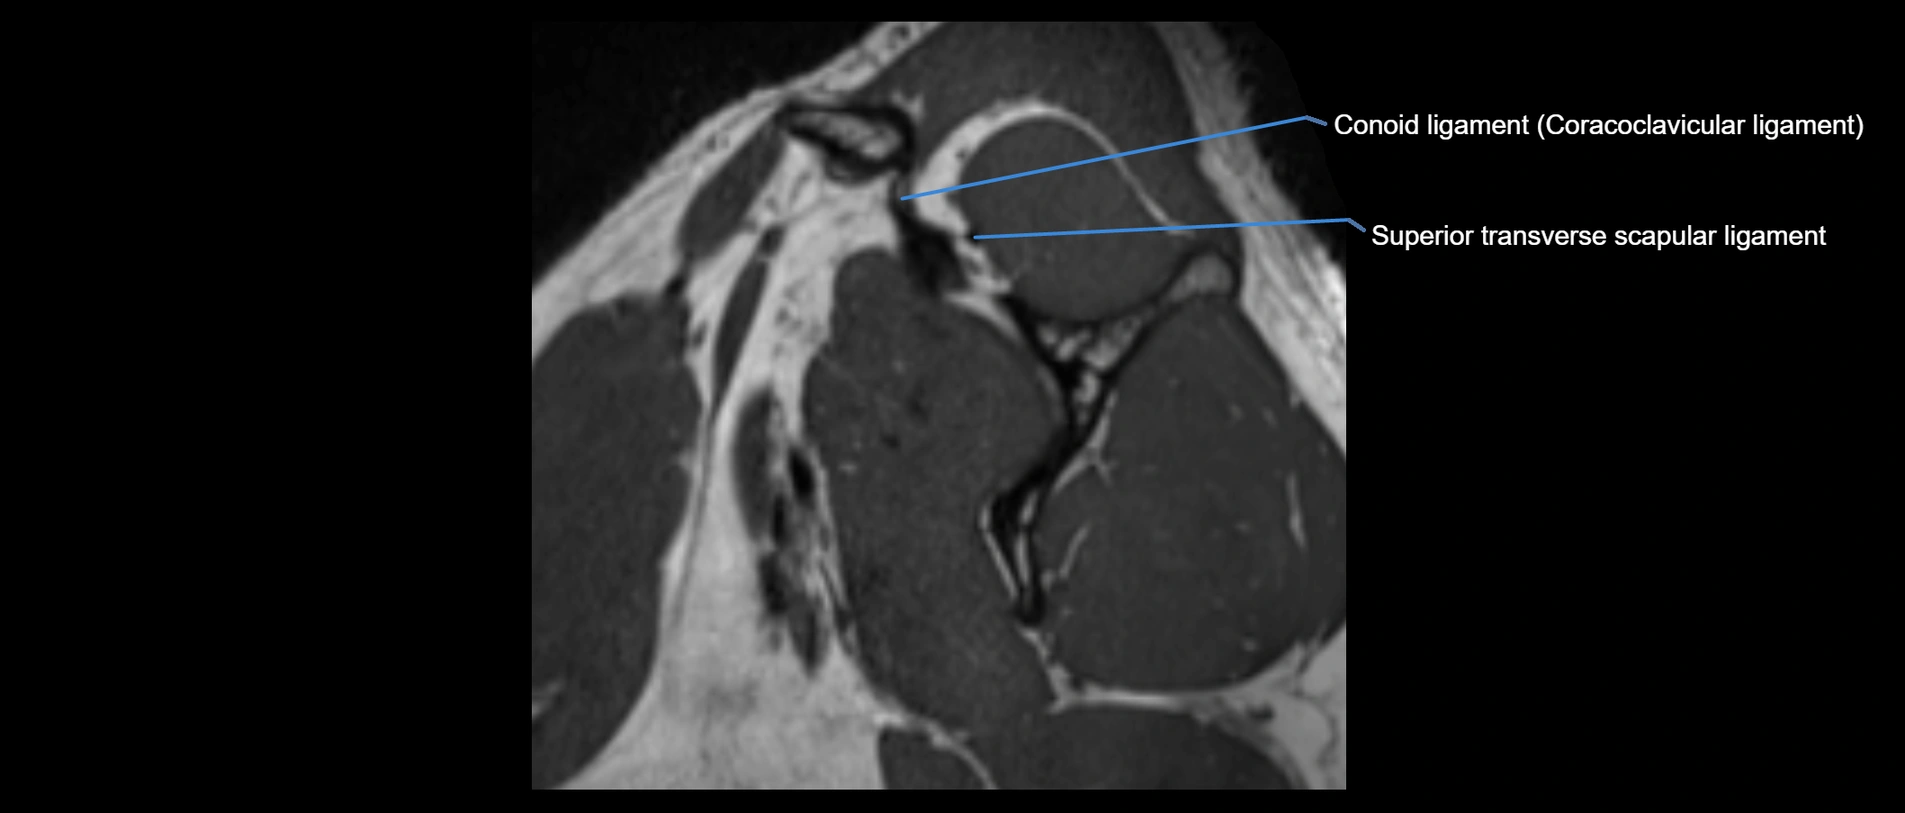

MRI images

image